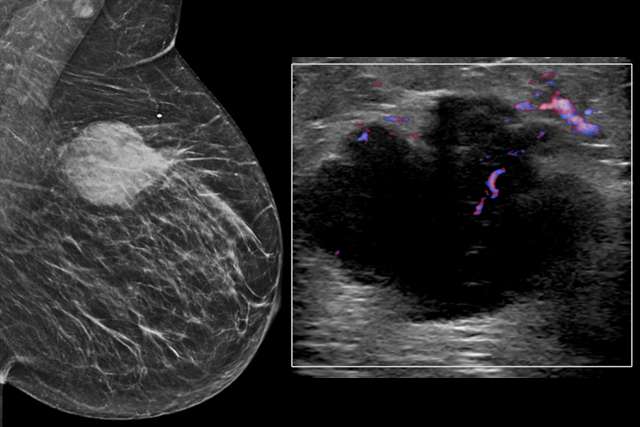

Evaluating patients presenting with lumps, pain, nipple discharge, and more.

Delve into cases developed by our section to uncover key clinical presentations and image findings that can help guide your practice.

National guidelines and supplemental resources to accompany your diagnostic imaging.